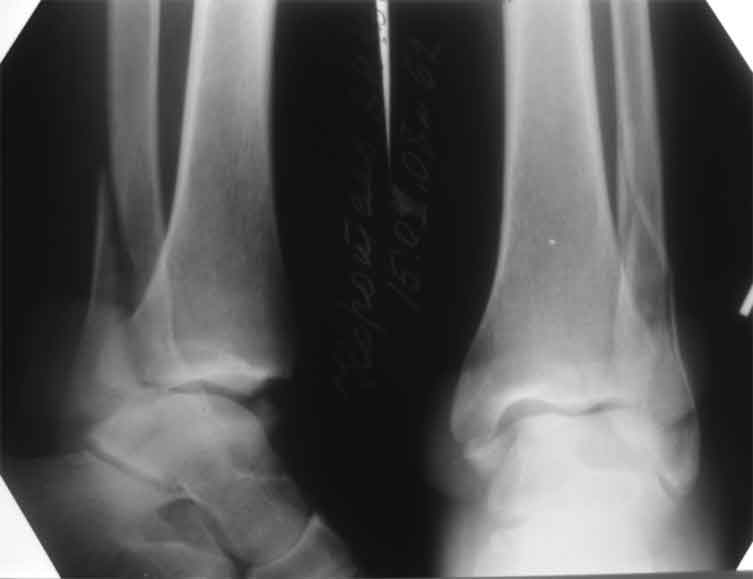

Мне кажется есть все основания попытаться сделать остеосинтез. Боль вследствие нестабильности. Нестабильность вследствие неанатомичного положения дистального отломка малоберцовой кости. Через 1,5 вполне возможно разобщить, репонировать и фиксировать длинный косой перелом наружной лодыжки. Вероятно, одновременно придется делать медиальный доступ для мобилизации внутренней лодыжки. Мы оперируем таких пациентов, функциональные (объем движений) результаты конечно хуже по сравнению с теми кого оперируем в первые 5-10 дней, но вполне удовлетворительные.

Согласен, на предоставленных рентгенограммах все основания для проведения открытого остеосинтеза.

сроки действительно небольшие, но если мы его и возьмем, то пройдет еще минимум неделя, кроме того смущает впечатление сращения н/лодыжки, похоже, что придется не разобщать,а остеотомировать, формирование оссификатов в полости сустава с медиальной стороны, да и сам пациент 1,5 месяца по поводу своей травмы сильно не напрягался

Сустав сохранный, я бы полечил. Молодой пациент, да и 1,5 мес - не

срок.